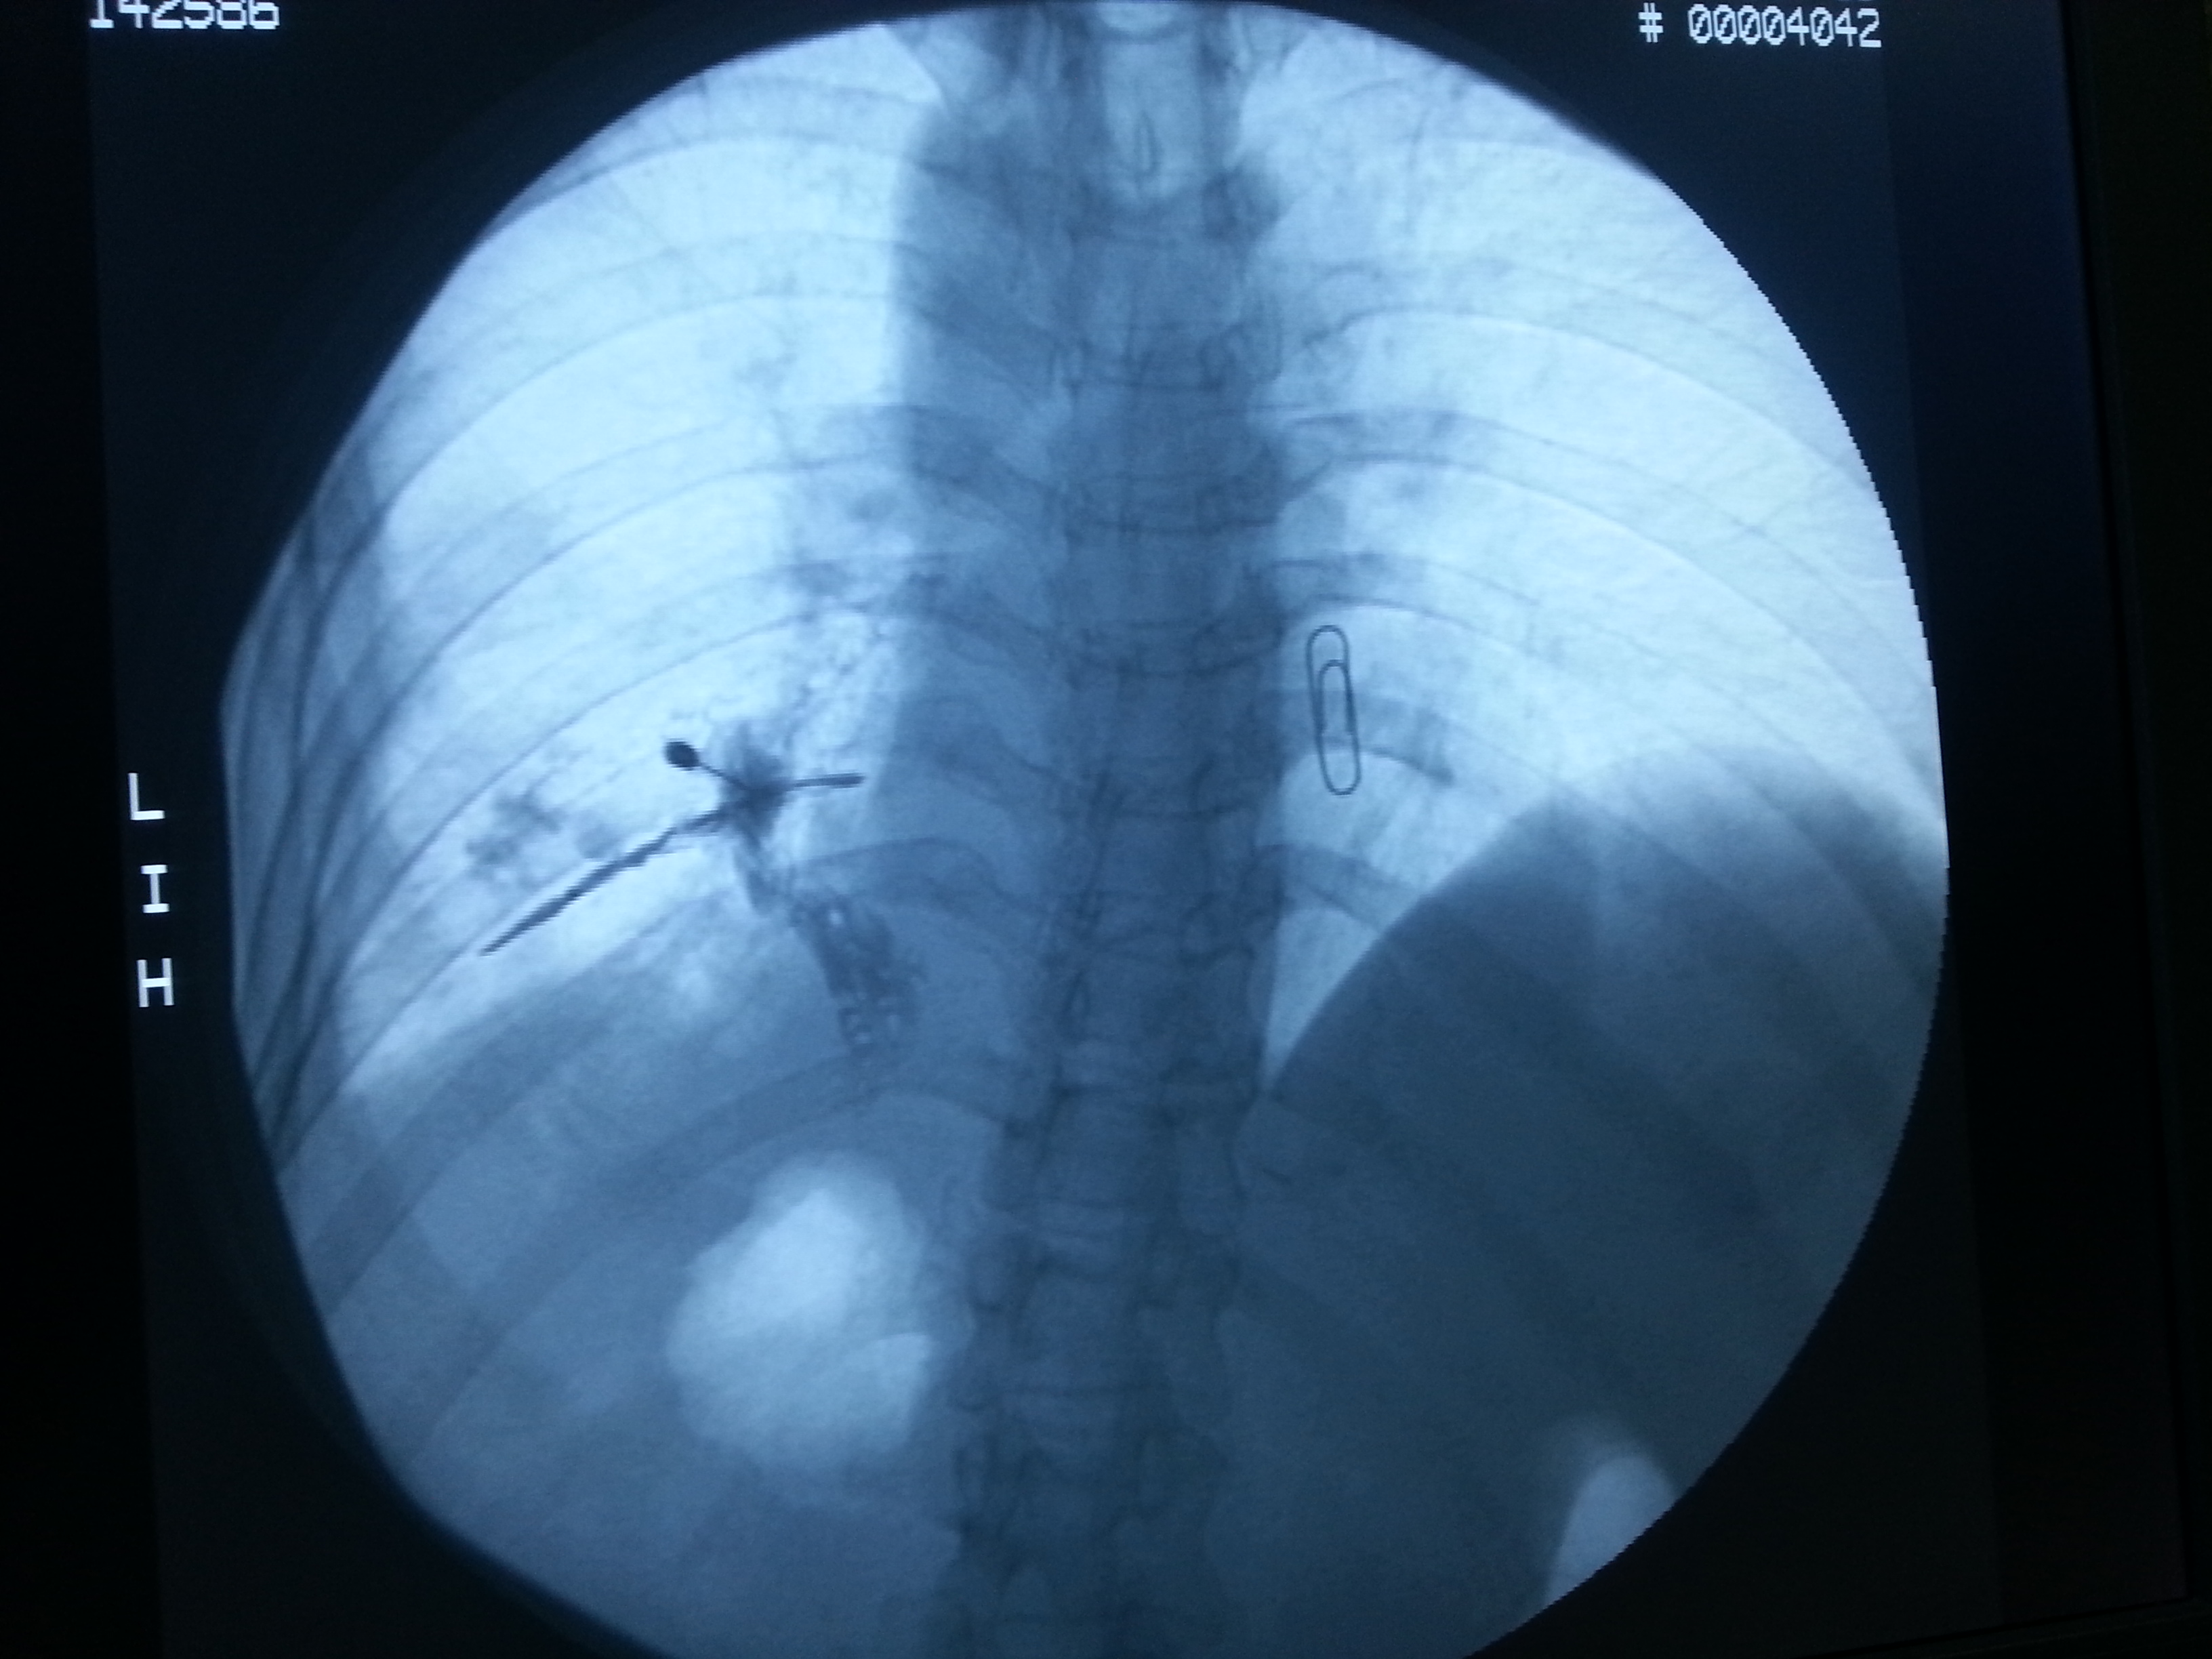

该病例为左肺癌多程治疗后左侧胸壁广泛疼痛的女性患者。为明确癌痛病因、疼痛来源及疼痛性质,麻醉诊疗组根据患者疼痛范围,明确诊断癌痛的性质及来源后,制定了癌痛三阶梯药物治疗+微创介入技术来控制管理癌痛的新方法,在DSA引导下对左侧肋间神经进行诊断性阻滞,取得良好效果。